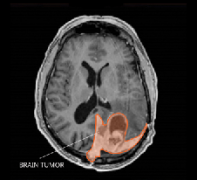

脑膜瘤 是常见的原发性中枢神经系统(CNS)肿瘤。脑膜瘤根据其特征分为三级。每个级别包括不同的脑膜瘤亚型。恶性脑膜瘤是指三级间变性脑膜瘤是恶性的...

脑膜瘤 是由覆盖大脑和脊髓的膜(脑膜)发展而来的脑瘤。它们是成人较常见的原发性脑瘤。大多数脑膜瘤(85- 90%)属于良性肿瘤,其余10- 15%属于非典型或恶性...

恶性脑膜瘤是指具有某些良性脑膜瘤的特点,逐渐发生恶性变化,呈恶性肿瘤的特点。恶性脑膜瘤的发生率占颅内脑膜瘤的0.9%~10.6%,平均为2.8%。 恶性脑...

恶性脑膜瘤有哪些,如何分类?什么是恶性脑膜瘤?恶性脑膜瘤,又称蛛网膜内皮瘤,是原发于颅内脑膜的肿瘤,约占颅内肿瘤的15.7%。了解恶性脑膜瘤的...